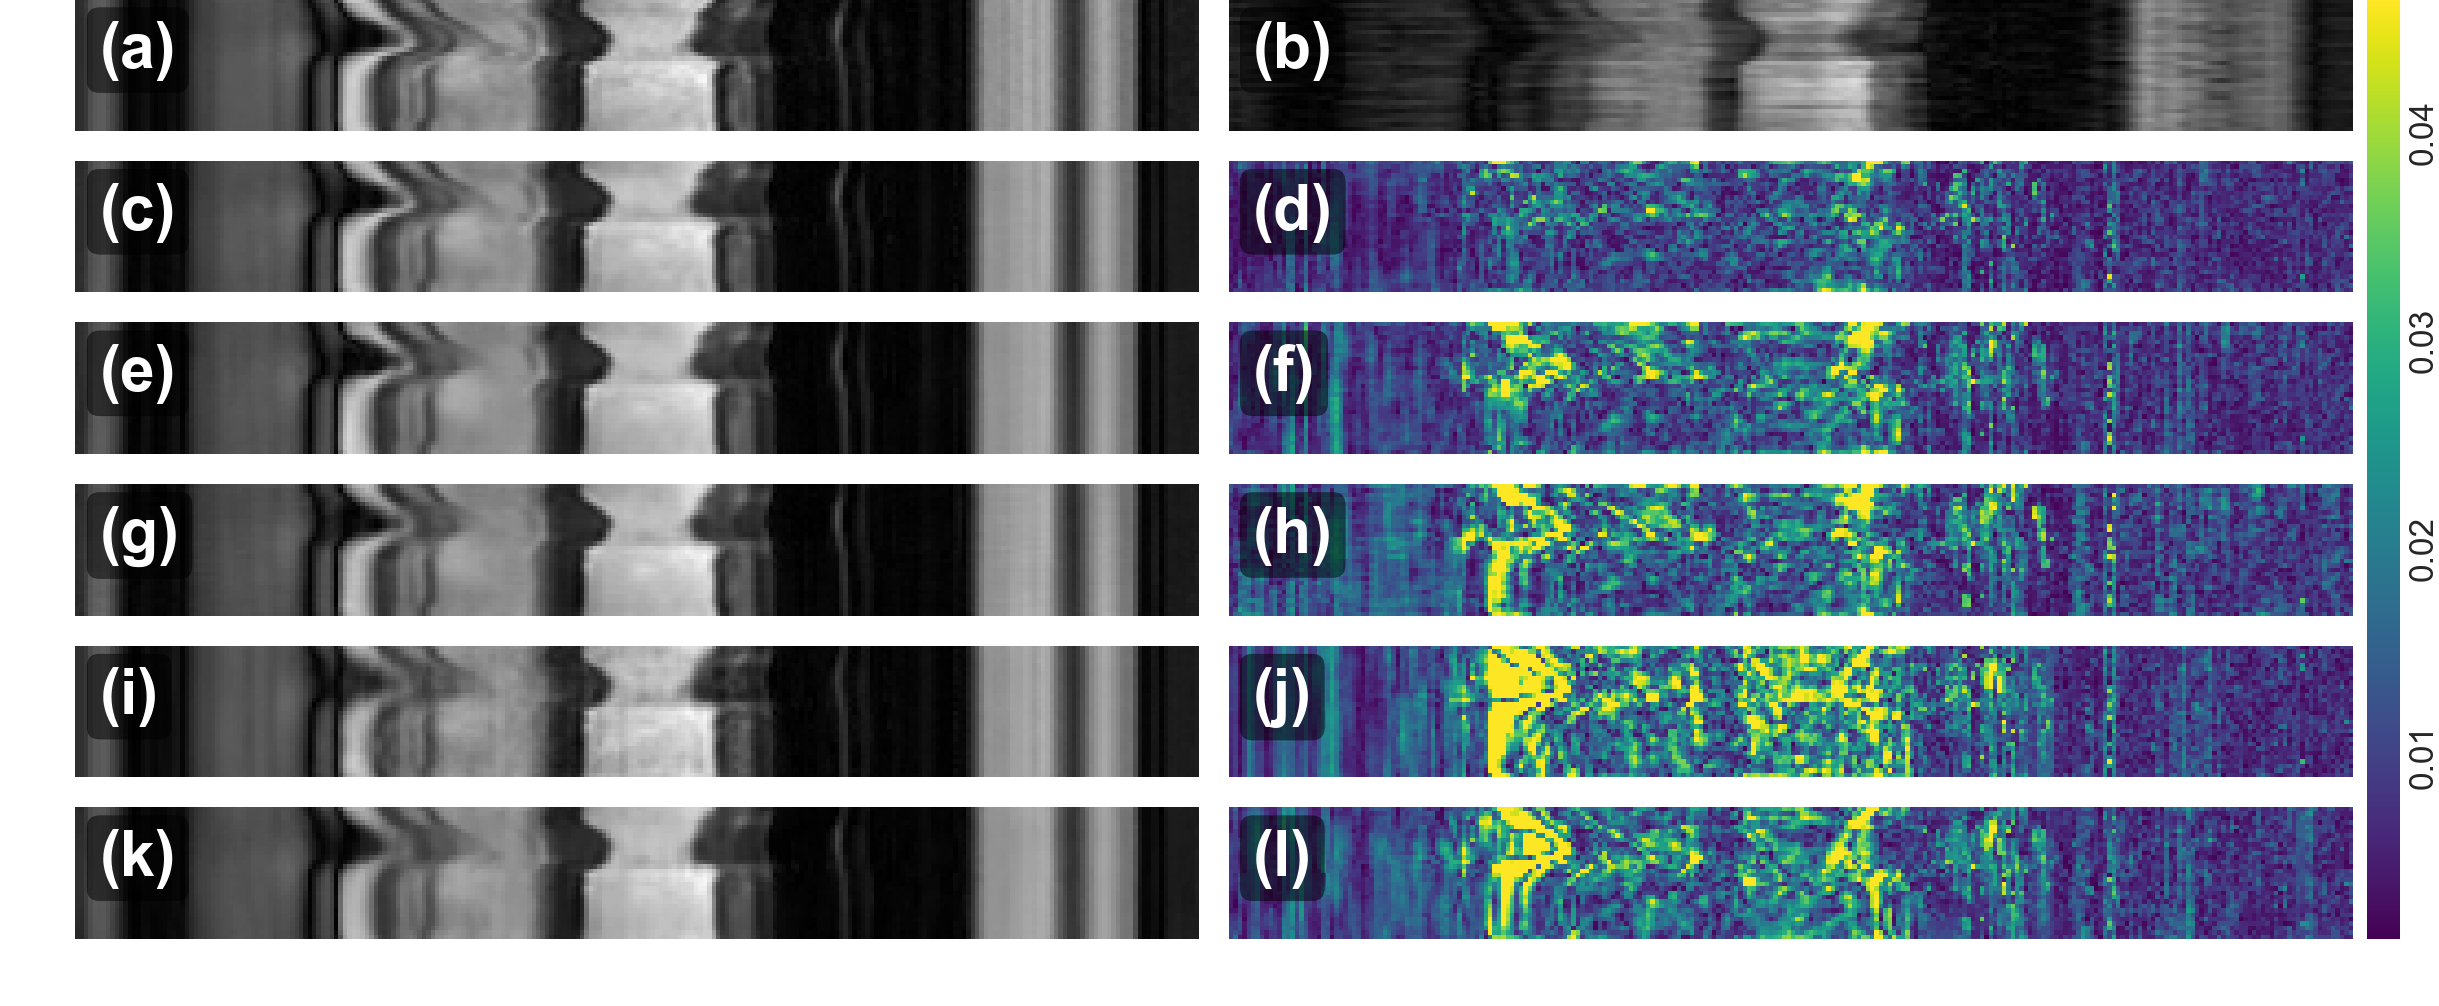

A comparison of the visualization results of a reconstruction from 9×9\times acceleration is shown in Fig. 5 with the reconstructed images and their corresponding error maps from different reconstruction methods. As one can see, our proposed model (Proposed-B) can produce more faithful reconstructions for those parts of the image around the myocardium where there are large temporal changes. This is reflected by the fact that RNNs effectively use a larger receptive field to capture the characteristics of aliasing seen within the anatomy. Their temporal profiles at x=120𝑥120x=120 are shown in Fig. 6. Similarly, one can see that the proposed model has overall much smaller error, faithfully modelling the dynamic data. It could be due to the fact that spatial and temporal features are learned separately in the proposed model while 3D CNN seeks invariant feature learning across space and time.

Figure 6: The comparison of reconstructions along temporal dimension with their error maps. (a) Ground Truth (b) Undersampled image by acceleration factor 9 (c,d) Proposed-B (e,f) 3D CNN (g,h) 3D CNN-S (i,j) k-t FOCUSS (k,l) k-t SLR